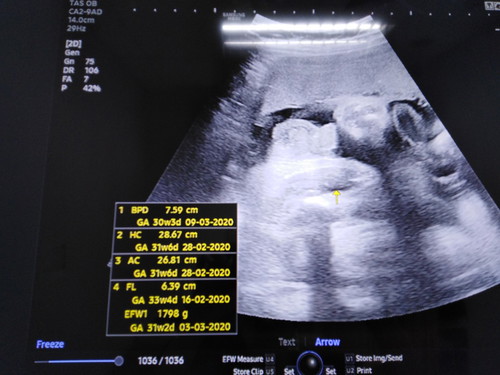

ตั้งครรภ์32+4weekเจ้าตัวน้อยบ้านอื่นหนักเท่าไหร่กันบ้างคะ?